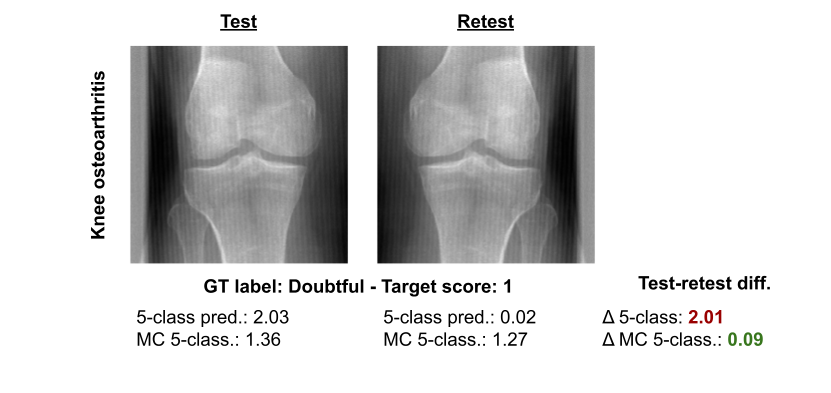

Figure 1 - Repeatability of knee osteoarthritis prediction for a selected example. Deep learning algorithms (5-class classification model with and without Monte Carlo (MC) dropout) were trained to predict the severity of knee osteoarthritis from x-rays. The image on the right is a horizontal flip of the image on the left. Below the images are the predictions generated using the two deep learning algorithms.

In Figure 1, we show an example with a low repeatability performance. We used the same deep learning algorithm to predict the severity of knee osteoarthritis (OA) from two X-rays of the same knee. The only difference between the images is that the X-ray on the right is a horizontal flip of the image on the left. The algorithm has been trained to predict the severity of OA on X-rays of left and right knees from the Multicenter Osteoarthritis Study, so we expect this flip not to affect the disease severity. However, the predictions are substantially different – returning, with high confidence, a value of 2 (mild OA) for the left and 0 (normal) for the flipped version of the image.  At the same time, an expert labeled the image as a 1 (doubtful). A reliable model should have produced the same prediction with little or no variability between the two images. Consequently, low test-retest repeatability of medical AI algorithms can lead to dangerous medical errors in clinical practice.

Through extensive experimental validation, we demonstrated that using Monte Carlo dropout leads to significantly higher repeatability without decreasing and, in some cases, even improving classification performance. We also found that because the severity classes are ordinal, most variability occurred for cases close to the decision boundary between two classes. When we used Monte Carlo dropout to re-train the same architecture, which had resulted in very different predictions for the example in Figure 1, the differences in the predictions between the two images dropped—from 2.01 to 0.09.  Additionally, the classification of the MC model agreed with the ground truth label.